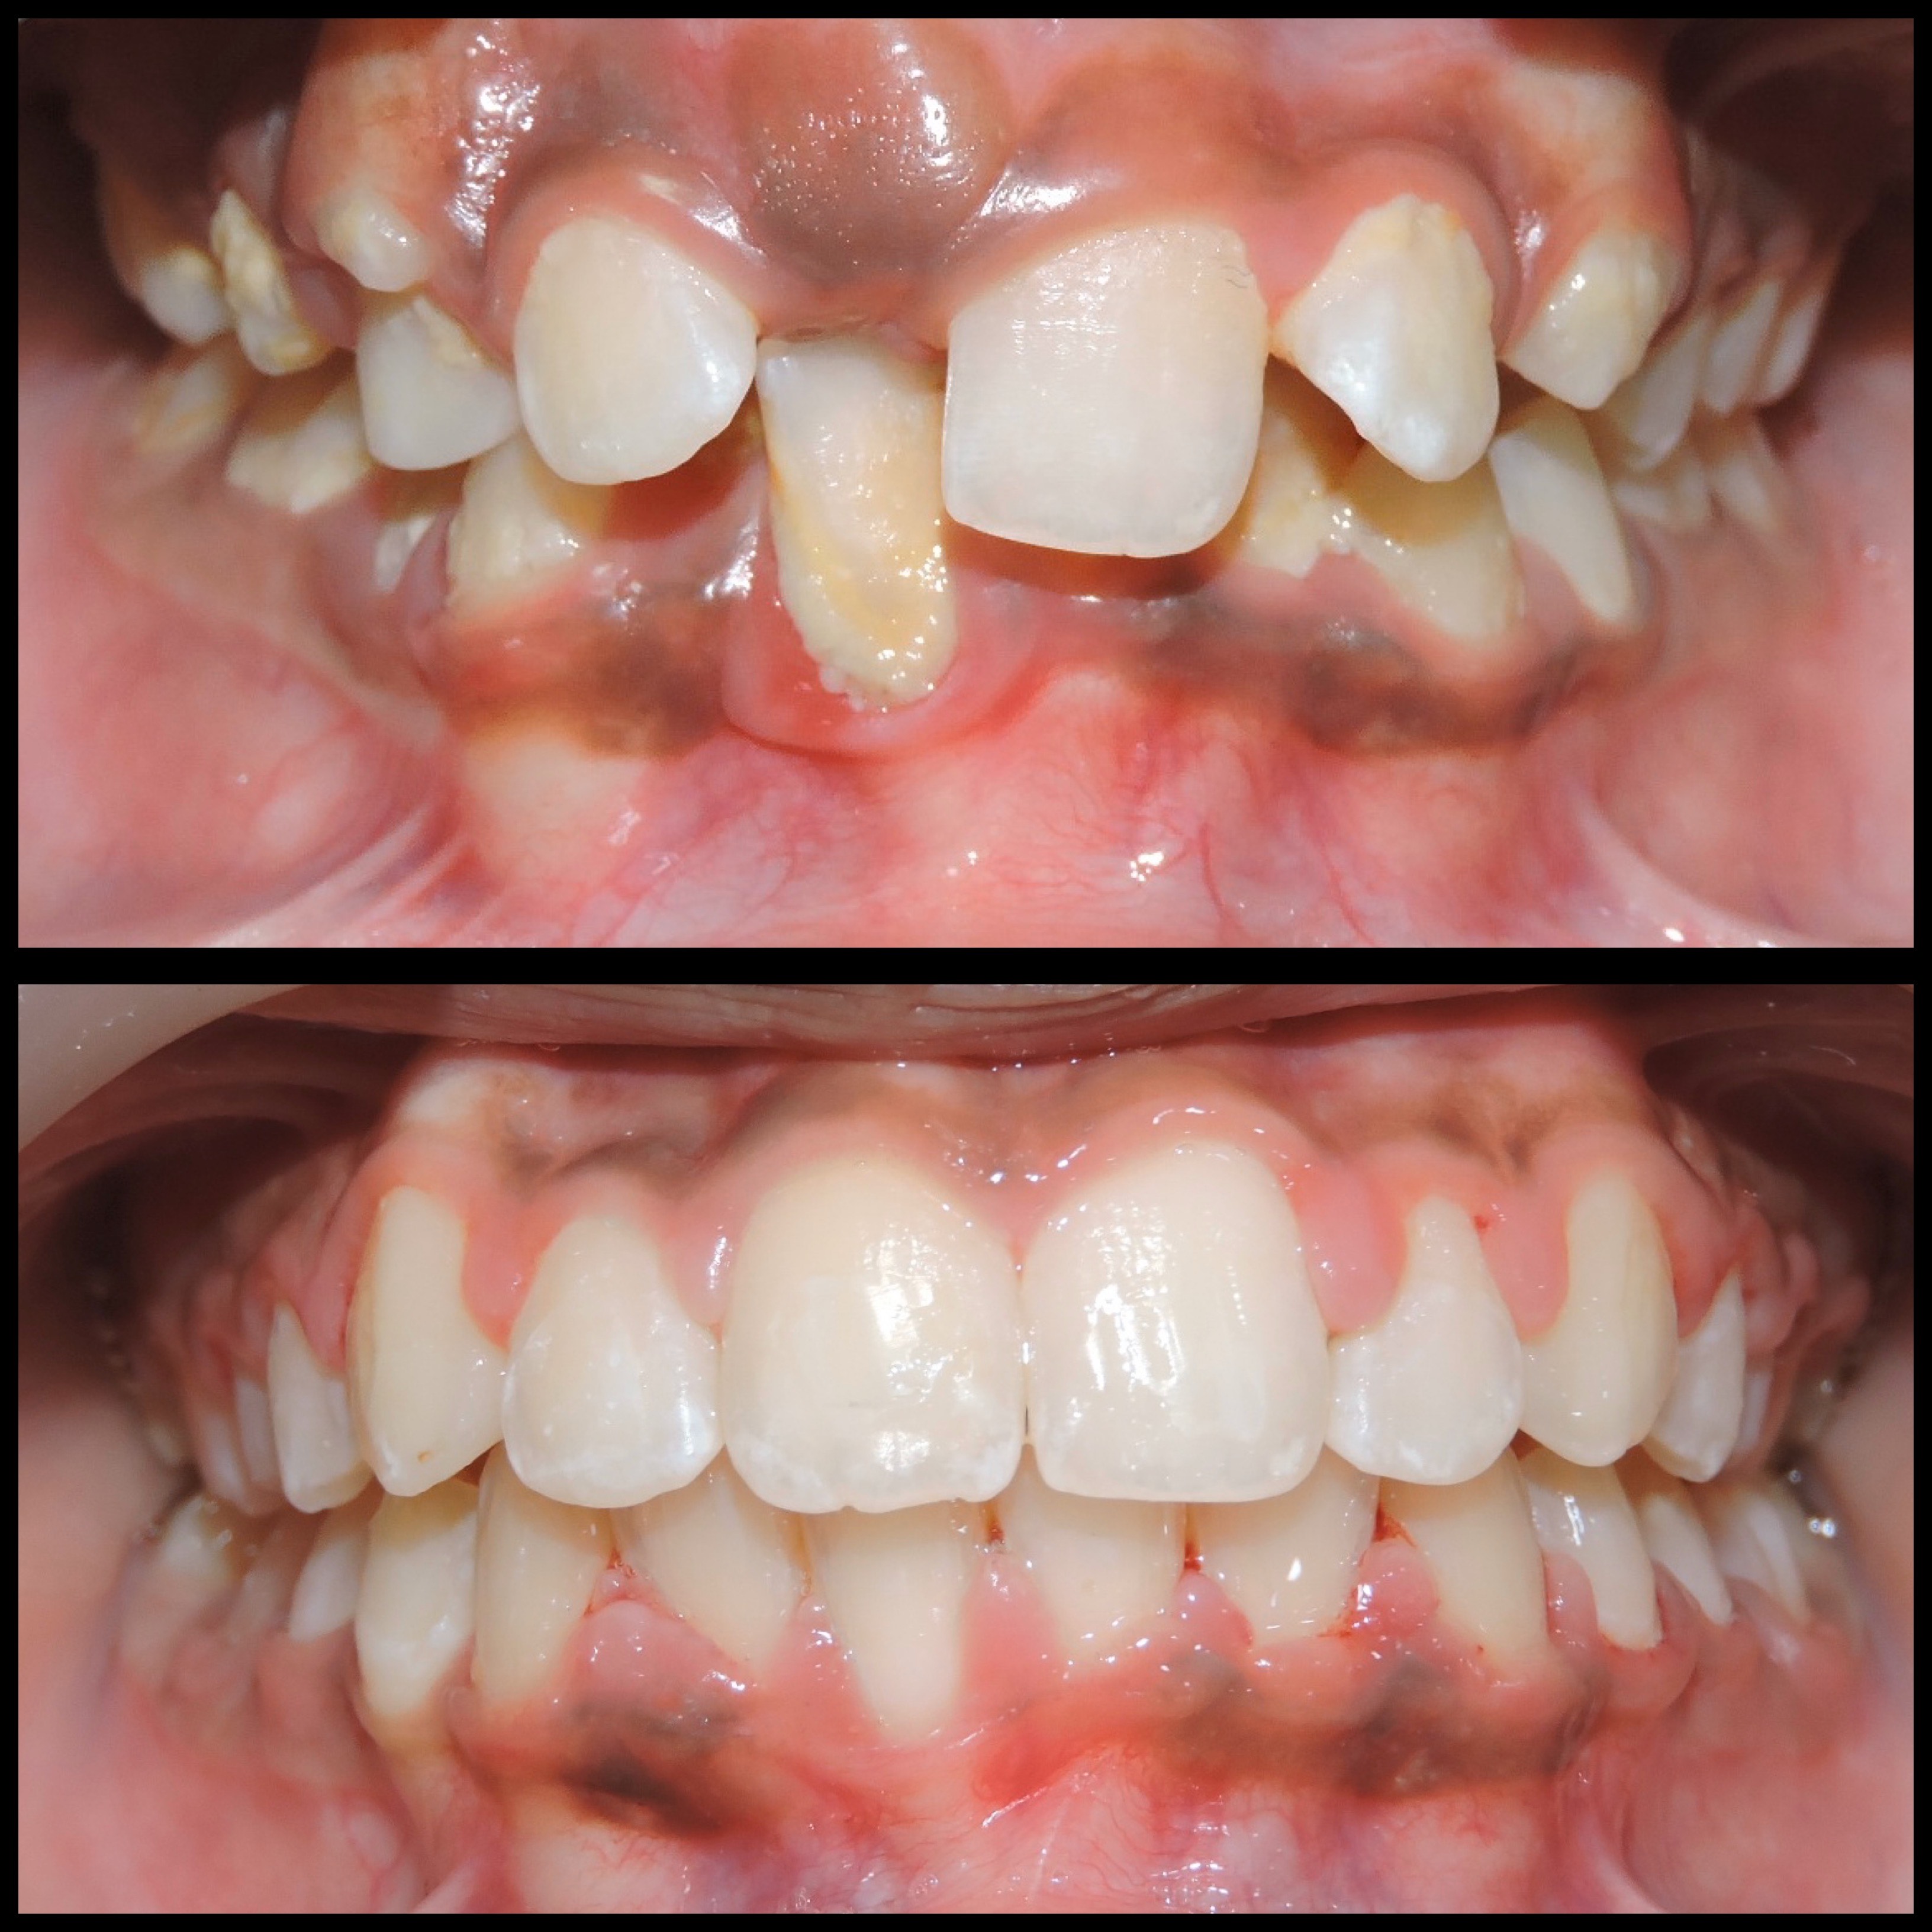

Gallery